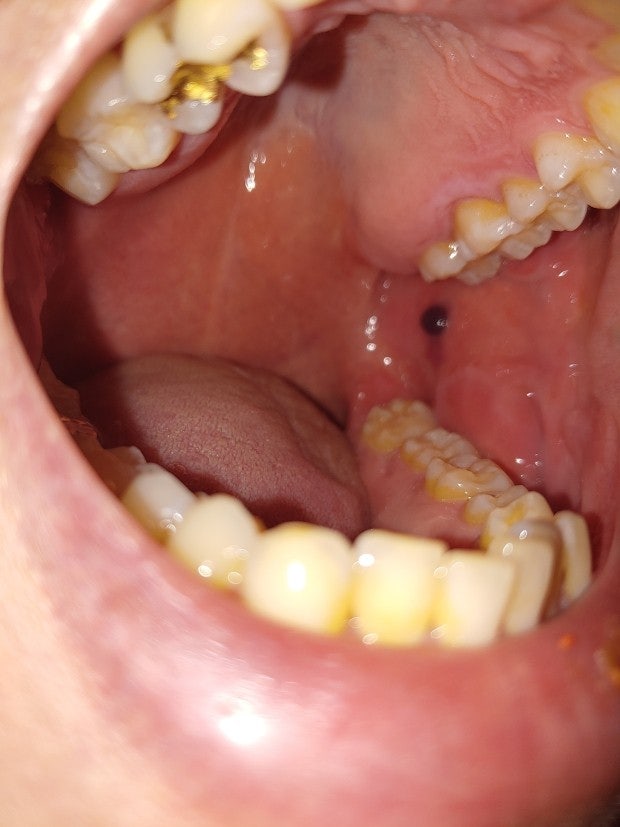

사진을 보시면 볼 안쪽에 무슨 검은 혹 같은 게 있습니다. (사진 가운데에서 약간 오른쪽 부분)

혀로 만져보면 혹 같은 느낌이 나는데 이게 뭘까요?

그냥 볼 살 씹어서 상처가 생겼다가 자연히 아무는 과정에서 부은 혹 일까요 아님 다른 질환의 증상일까요

우선, 씹다가 생긴 상처가 부풀어 오른 것이거나, 물리적인 자극으로 인한 염증일 수 있습니다. 그러나 검은색을 띤 경우, 구강 내에서 발생할 수 있는 종양이나 낭종, 혹은 색소침착일 가능성도 있어요

일반적으로 피주머니를 의심해볼 수 있는 소견입니다. 언급하신 것처럼 볼 살을 씹고 난 이후 회복이 되는 과정에서 생길 수 있을 법한 소견입니다. 정확한 것은 이비인후과에서 구체적으로 제대로 진료 및 검진을 받아보아서 감별 진단을 받으시는 것이 필요할 것으로 사료됩니다.